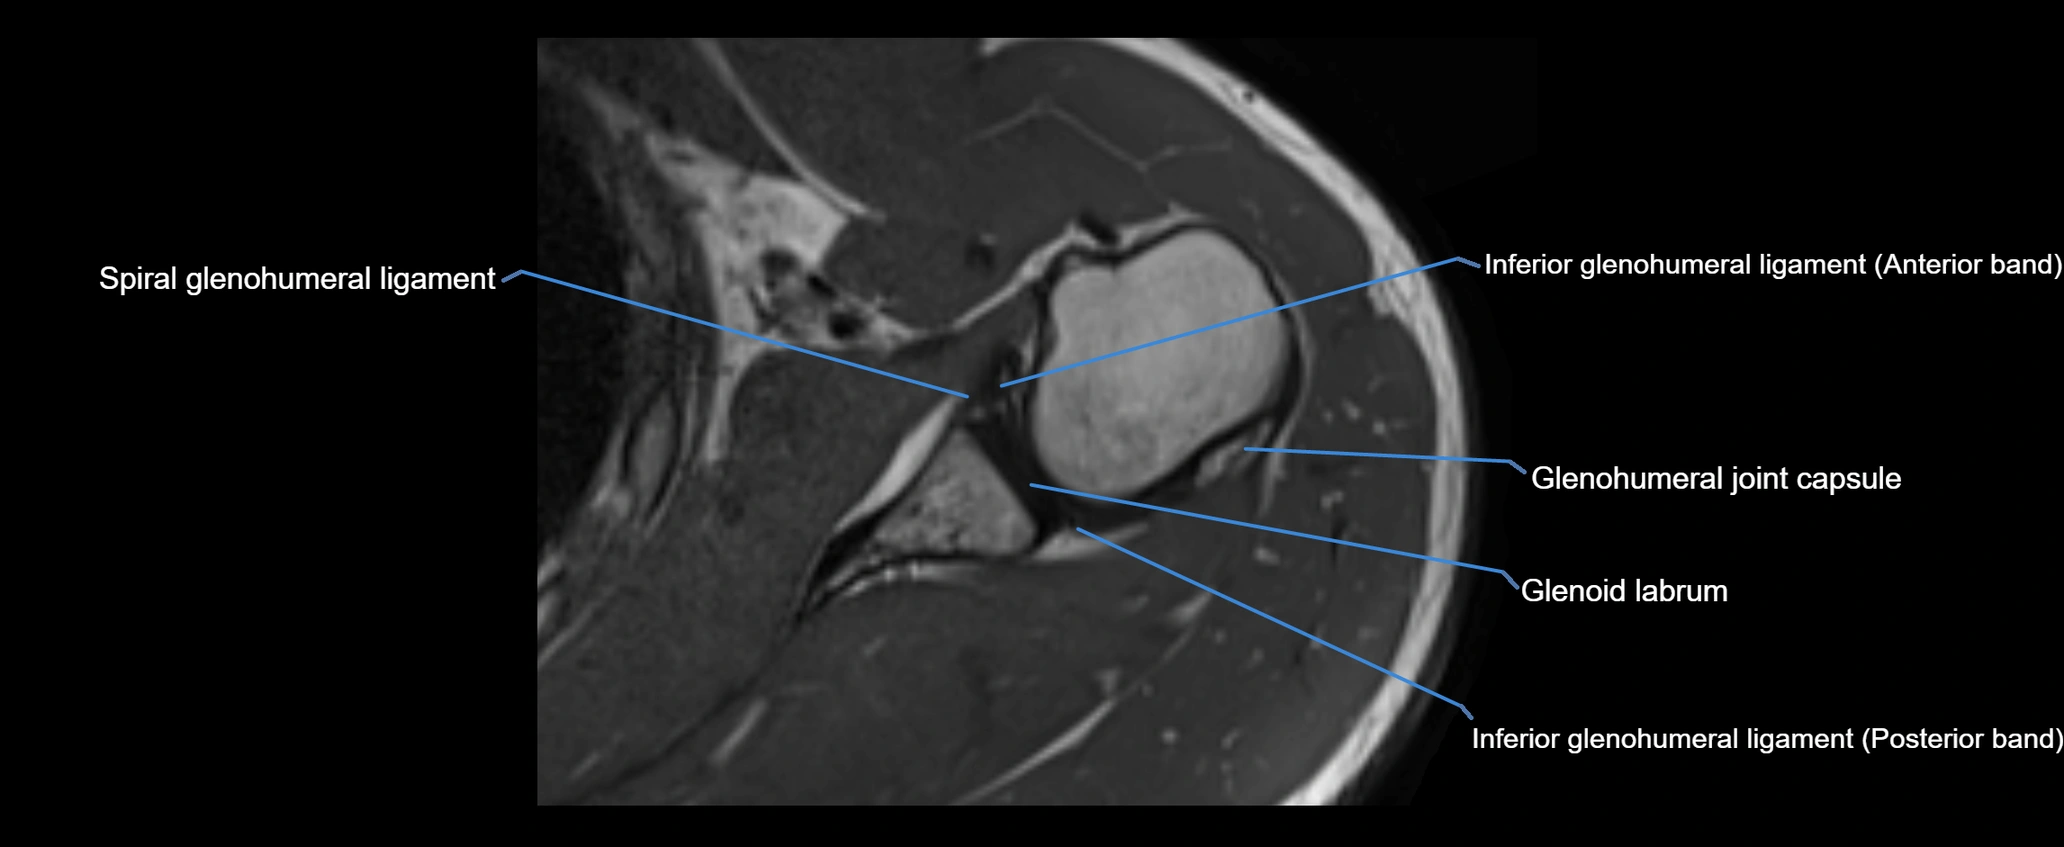

CT image

image